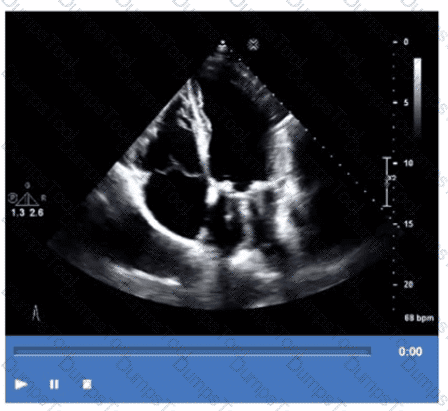

What is the regional wall motion assessment of the two-chamber view displayed in this video?